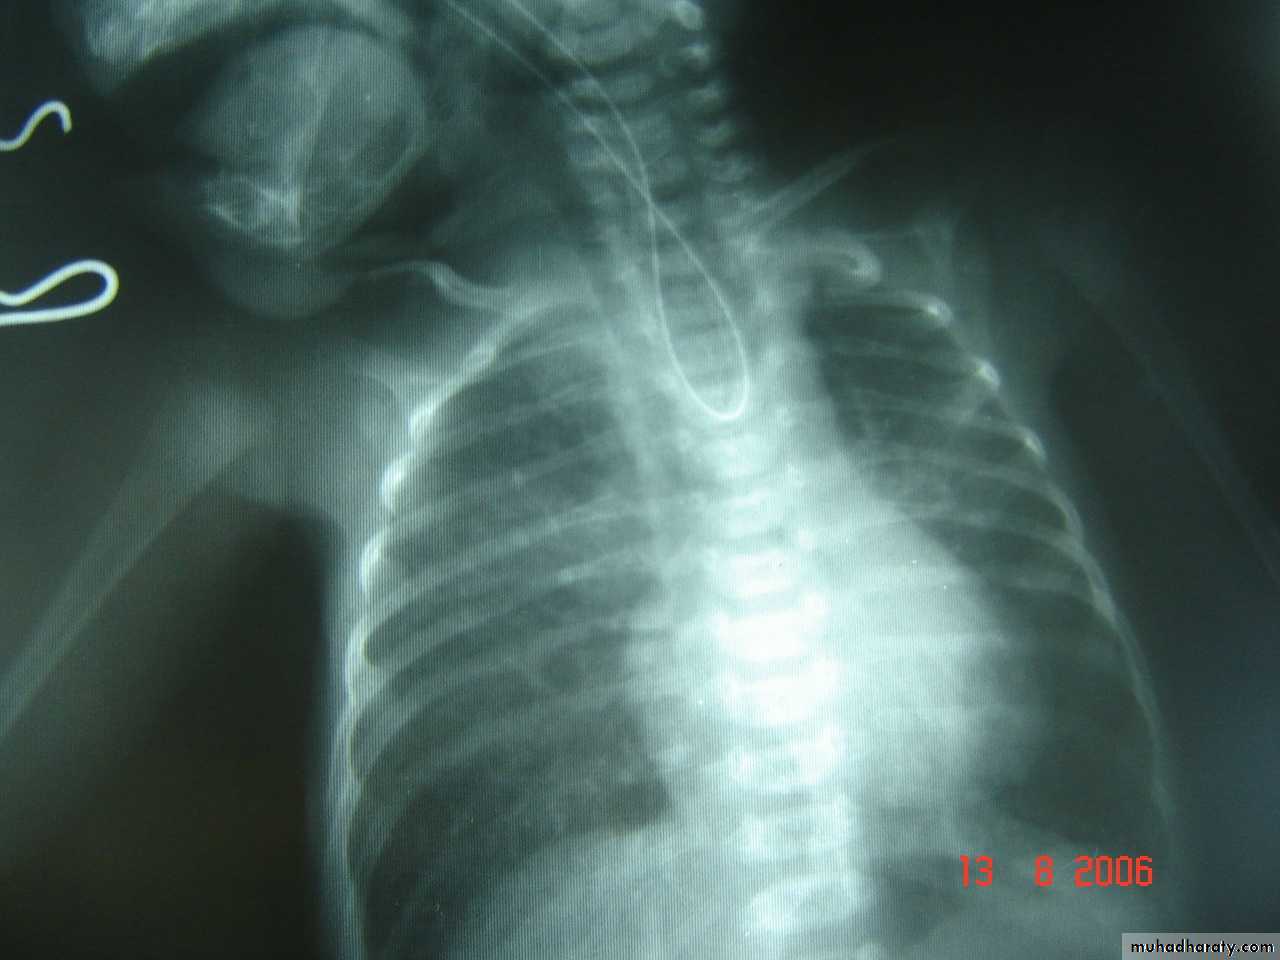

Respiratory Distress in the Newborn

Oesophageal Atresia and Tracheo-Oesophageal Fistula,